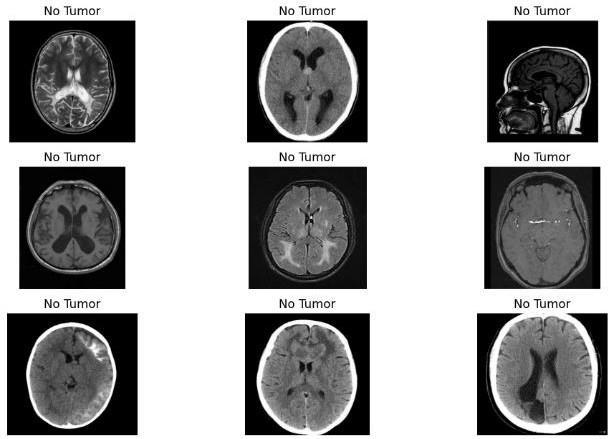

For this experiment, we utilized a diverse dataset comprising MRI images of the brain, including both cancerous and non-cancerous cases. The dataset was carefully curated to encompass a wide range of tumor types,sizes,andlocations,ensuringthediversitynecessary fortrainingandevaluatingtheSVMmodeleffectively. Fig.2.Samplestestedfornotumor.

The SVM Model is trained on the training data of chosen dataset,Fig2showsresultsoftestingofSVMmodelonthe testingdataofchosendatasetfornotumor.